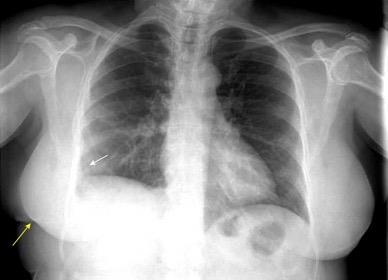

Masa axilar izquierda y derrame pleural derecho. Implantes pleurales, paraespinales . Ganglios en mamaria interna. Linfoma B difuso

Jaffe ES. Diagnosis and Classification of Lymphoma: Impact of Technical Advances.

2005. Masa pulmonar.